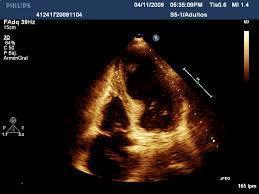

AQUINESIA APICAL POR ECOCARDIOGRAMA

takotsubo

aquinesia apical